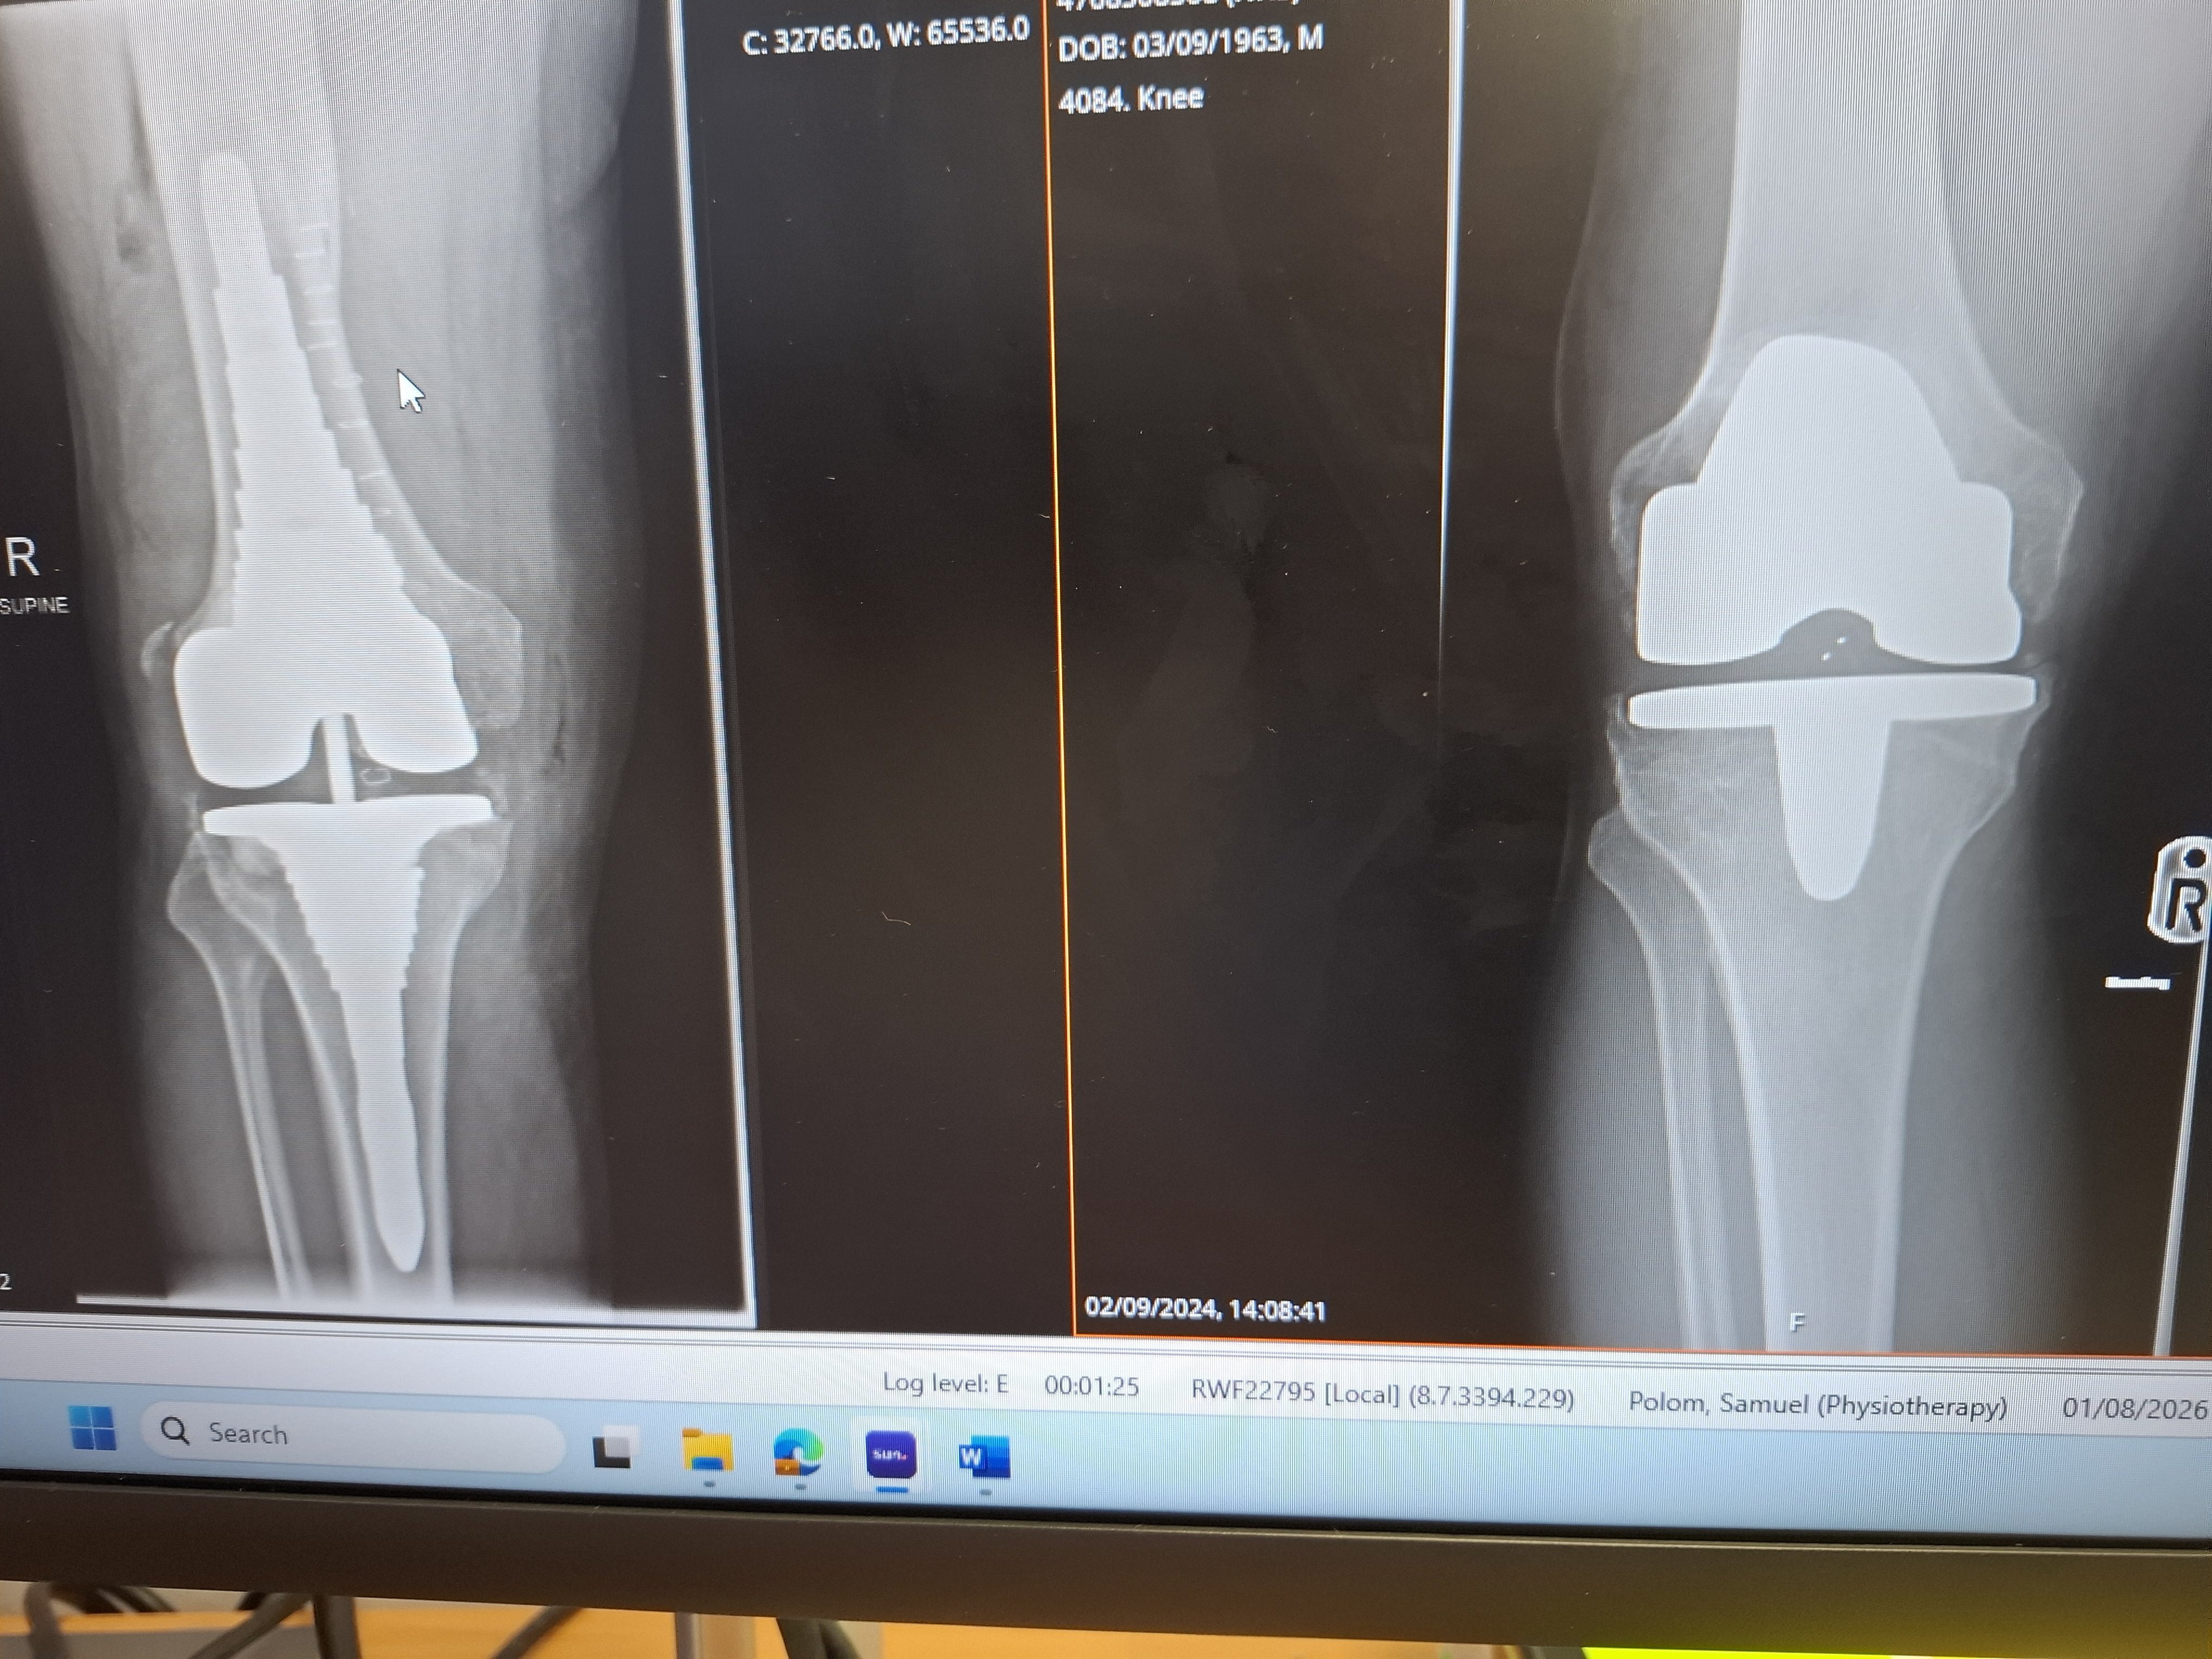

Yes, finally back. New knee seems good. I'm still hobbling but bending is good . Finding the Kawasaki a little heavy but nothing i can't handle. I still think my first knee took longer to settle than this one even though this one is much bigger. ( a replacment of a replacment )

As you can see by the pics (old on the left) i had the op 19th Decmember.so.3 months to get to riding again. 20260404_121640.jpg 20260108_102554.jpg

The new one looks a lot more anchored and supportive of the surrounding bone structure, congratulations and hopefully you'll be back to full mobility shortly.